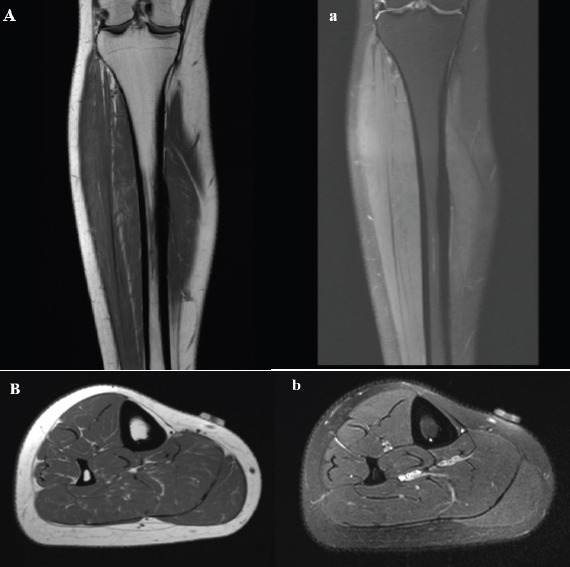

Case report: A 31-year-old female presented to our clinic with chronic neuropathic pain after sustaining a blunt injury to the medial aspect of the right leg 15 years previously while playing softball. Her pain was localized to the anteromedial lower leg and was not relieved by medical management and therapy. She temporarily had complete relief of her symptoms with ultrasound-guided hydrodissection. She was treated with surgical exploration and neurolysis, and postoperatively, the patient had no complications and complete relief of her pain.

Conclusion: We present a case of a 31-year-old patient who had perineural scarring and chronic neuropathic pain necessitating surgical exploration and neurolysis. Our case highlights the importance of investigating the etiology of neuropathic pain with several modalities and demonstrates the utility of ultrasound-guided peripheral nerve hydrodissection for both therapeutic and diagnostic purposes.